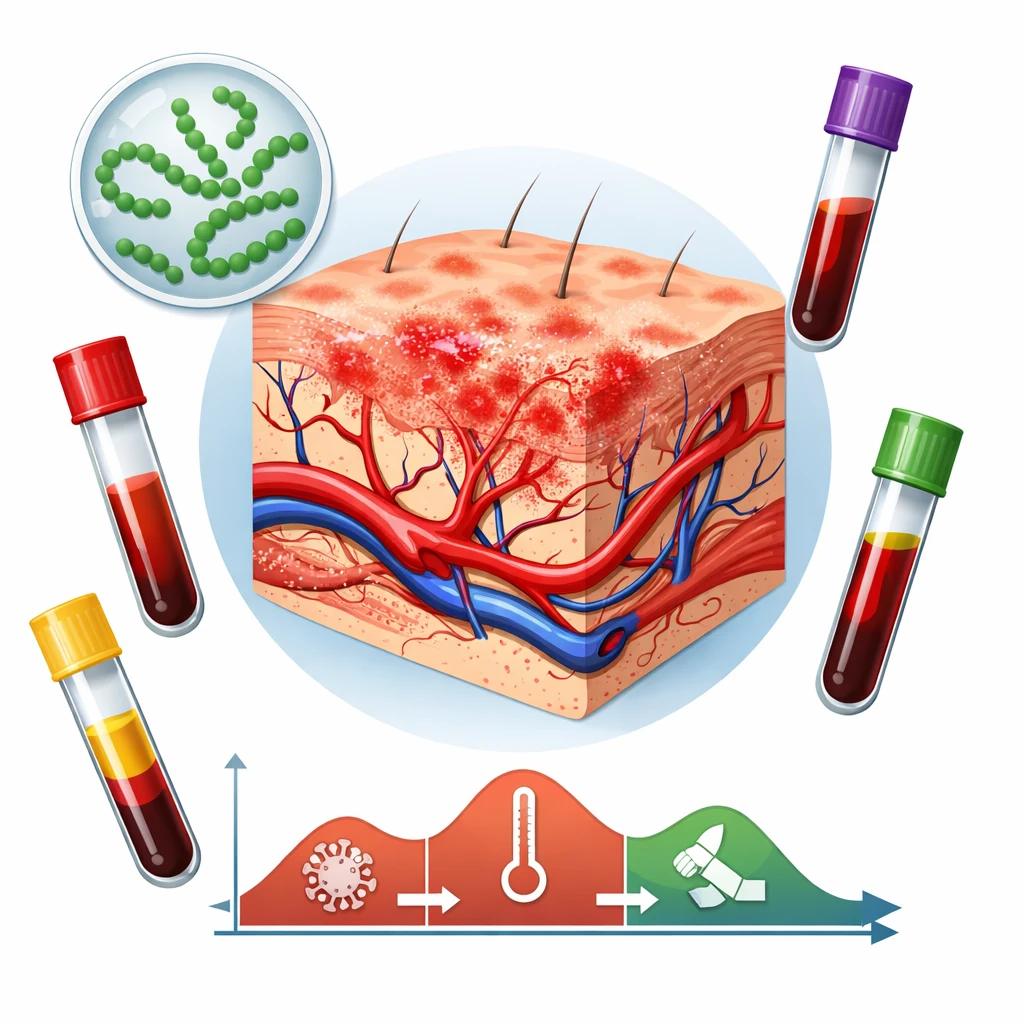

آزمایش سرولوژی لیستریا با اندازهگیری آنتیبادیهای IgM و IgG علیه باکتری انجام میشود.

کاربردهای اصلی

- کمک به تشخیص تماس اخیر یا قبلی با لیستریا

- استفاده تکمیلی در کنار کشت خون، علائم بالینی و سونوگرافی

تفسیر کلی نتایج سرولوژی لیستریا

- IgM مثبت یا رو به افزایش:میتواند نشاندهنده عفونت اخیر یا فعال باشد

- IgG مثبت با IgM منفی:معمولاً بیانگر تماس قدیمی است

- افزایش تیتر آنتیبادی در نمونههای متوالی:به نفع عفونت فعالتر تفسیر میشود

✅ تفسیر نتایج حتماً باید در کنار وضعیت بالینی مادر و یافتههای جنینی انجام شود.